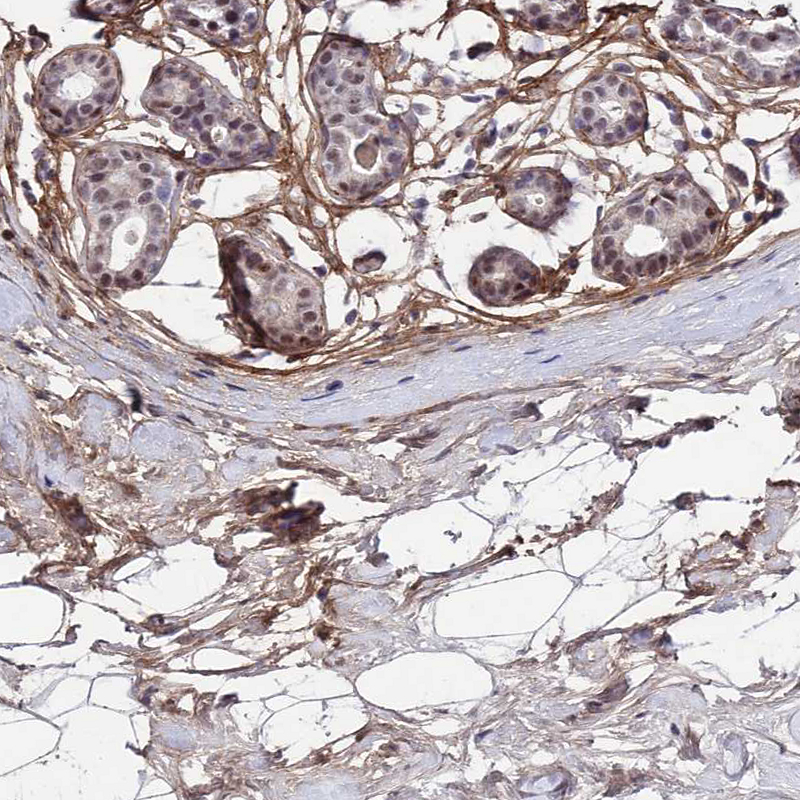

Immunohistochemical staining of human lung shows moderate to strong membranous positivity in pneumocytes.